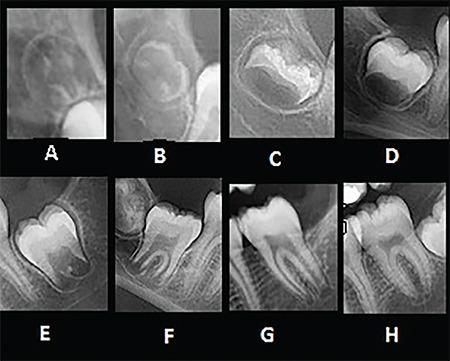

This retrospective study was conducted on panoramic and lateral cephalometric images of 406 female patients aged 9-14 years. The skeletal maturity and calcification stages of the mandibular canines, first premolars, second premolars, and second molars were determined using the Hassel-Farman and Demirjian (DI) methods, respectively. The prediction accuracy of the peak pubertal stage with the studied teeth was assessed using a receiver operating characteristic curve and the area under the curve (AUC). The DI stage of H was designated as the reference level, and Bayesian logistic regression analysis was used to assess the coinciding chance of each DI stage and peak pubertal stage.

The AUC range of studied teeth was 0.84-0.92 in predicting peak pubertal stage (all p<0.001). In the canines and first premolars, the coinciding chance of peak pubertal stage and stage H was significantly higher than that in other stages [p<0.05, odds ratio (OR) ≤0.14]. In the second premolars and second molars, the chance of peak pubertal stage coinciding with stages H and G did not significantly differ (p>0.05); however, the chance of stage G coinciding with peak pubertal stage in the second molars was higher than in stage H (OR=4.59).

Stage H in all studied teeth and stage G in the second premolars and second molars predict peak pubertal stage with high accuracy. Considering that stage H is the end of tooth calcification stages and the accuracy of predicting stage G of second molar teeth is higher than the above stage, estimating the peak pubertal stage is recommended by the second case.